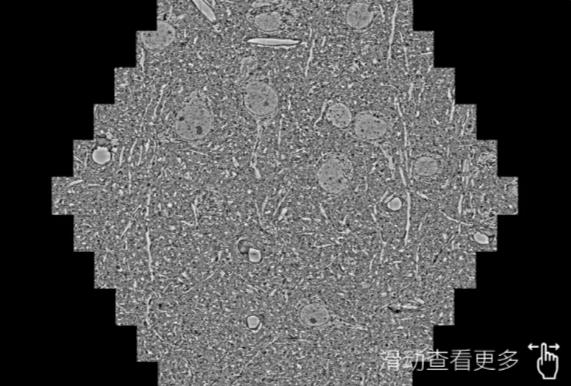

鼠脑切片。左图使用和田蔡司和田扫描电镜MultiSEM706对165μmx143pm面积区域成像,耗时仅需1.5秒。右图为鼠脑切片中30μm区域放大效果。样品由芝加哥大学B.Kasthuri提供。